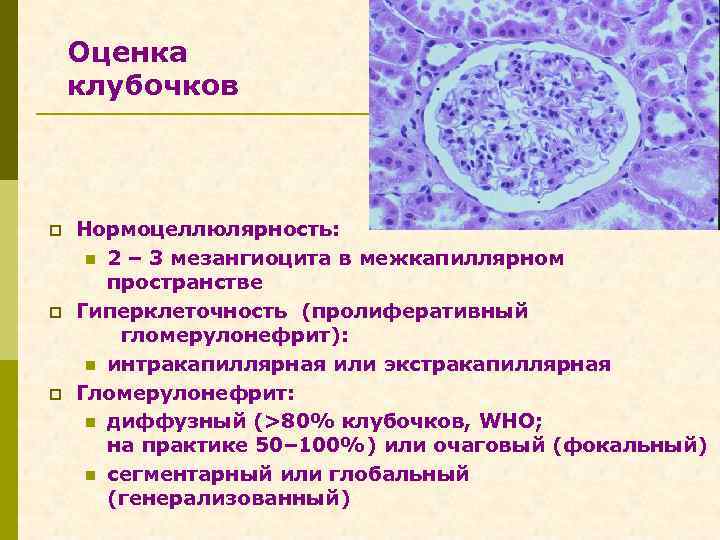

Оценка клубочков p p p Нормоцеллюлярность: n 2 – 3 мезангиоцита в межкапиллярном пространстве Гиперклеточность (пролиферативный гломерулонефрит): n интракапиллярная или экстракапиллярная Гломерулонефрит: n диффузный (>80% клубочков, WHO; на практике 50– 100%) или очаговый (фокальный) n сегментарный или глобальный (генерализованный)